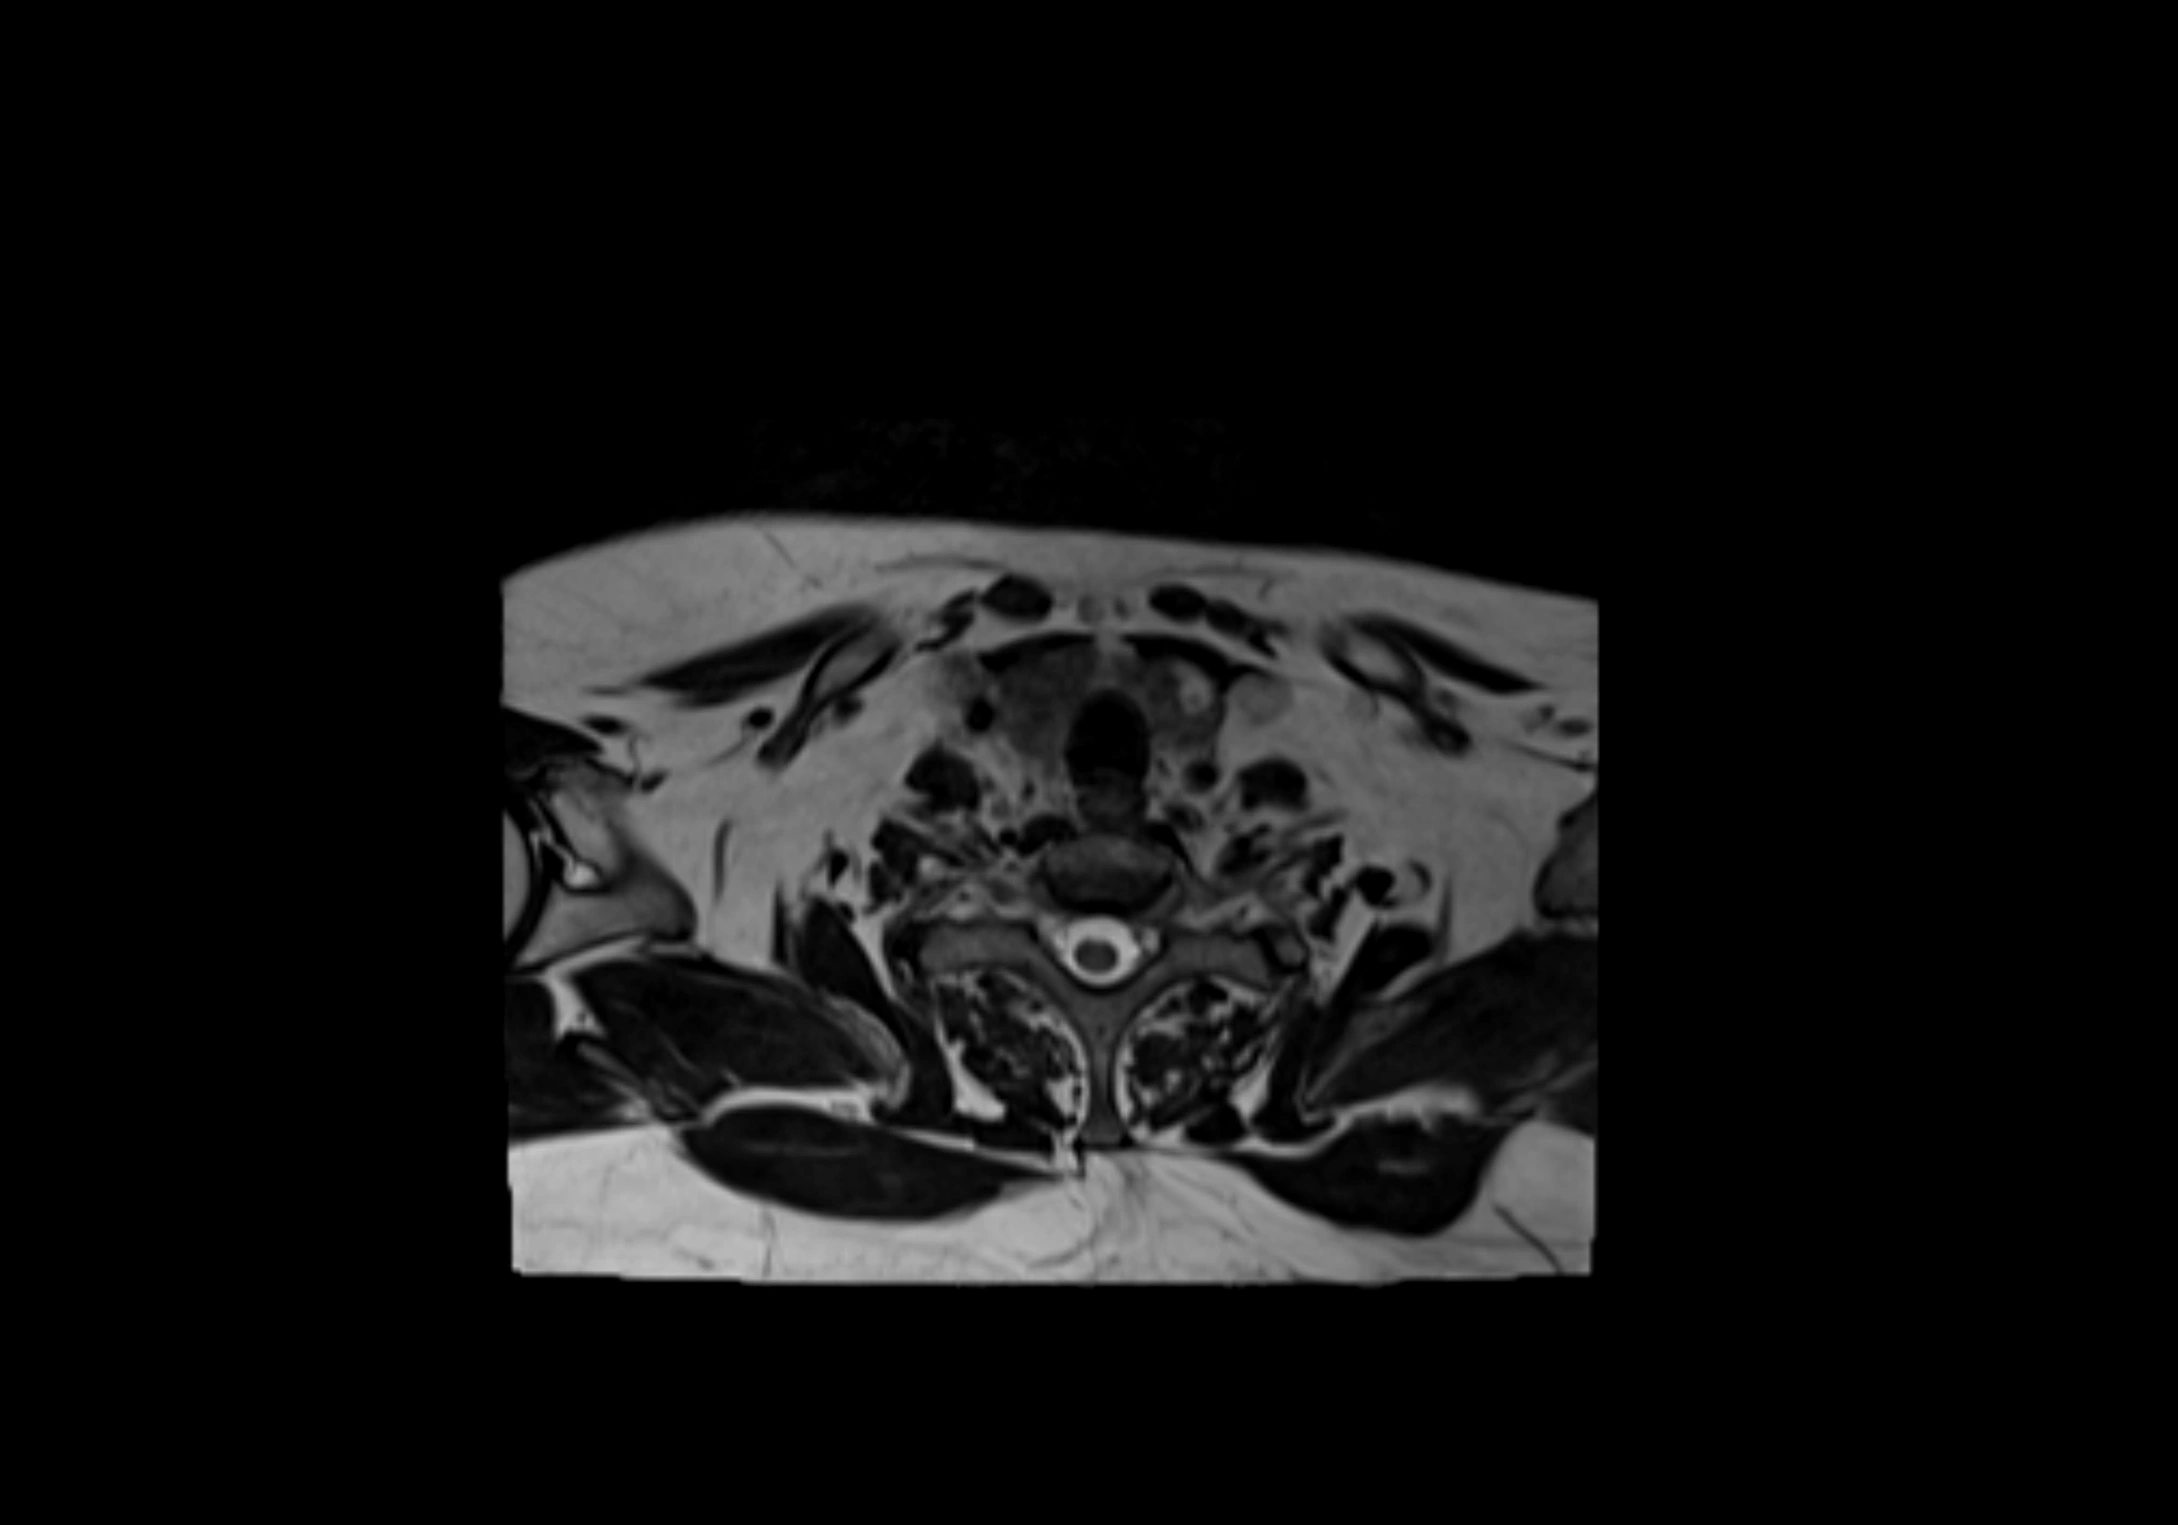

MRI Appearance

T1-weighted images:

• Normal accessory nodes appear as small, oval hypointense to intermediate signal structures within subcutaneous fat

• Surrounded by hyperintense fat, enhancing contrast for visualization

• Pathological nodes may appear enlarged or rounded, sometimes with cortical thickening

T2-weighted images:

• Nodes show intermediate signal, with surrounding fat bright

• Useful for detecting edema, inflammation, or infiltration

• Fatty hilum may appear slightly hyperintense relative to cortex